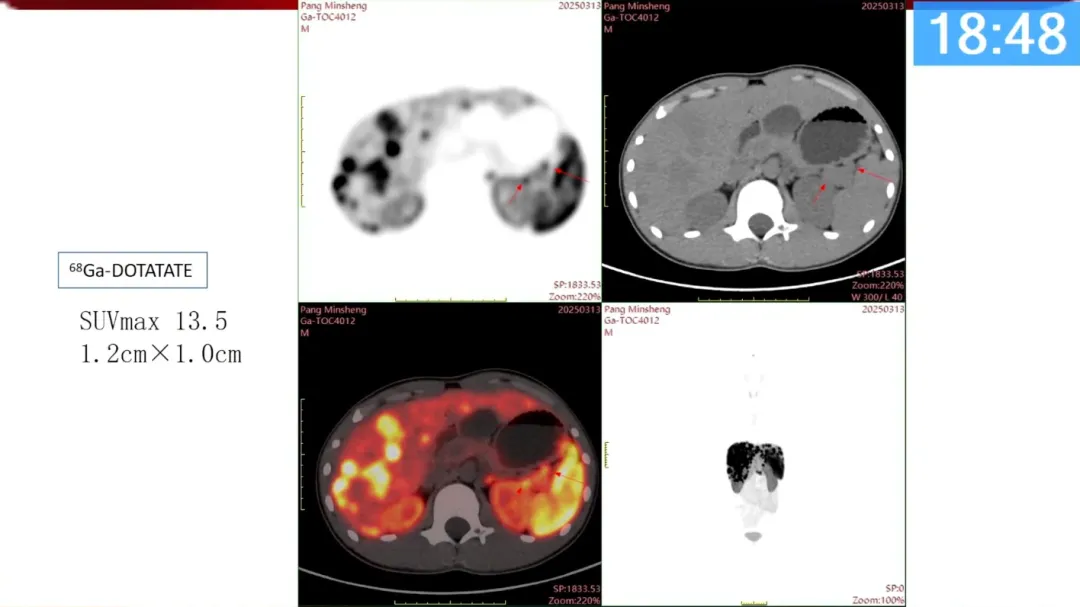

于江媛:神经内分泌肿瘤的核医学应用(30P)

张盼盼:神经内分泌肿瘤病例分享(32P)